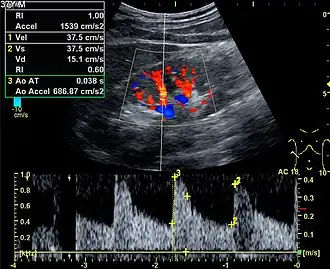

%252C_diastolic_velocity_(Vd)%252C_acceleration_time_(AoAT)%252C_systolic_acceleration_(Ao_Accel)_and_resistive_index_(RI)_of_normal_kidney.jpg)

Doppler ultrasonography is widely used in renal ultrasonography. Renal vessels are easily depicted by the color Doppler technique in order to evaluate perfusion. Applying spectral Doppler to the renal artery and selected interlobular arteries, peak systolic velocities, resistive index, and acceleration curves can be estimated (Figure 4) (e.g., peak systolic velocity of the renal artery above 180 cm/s is a predictor of renal artery stenosis of more than 60%, and a resistive index, which is a calculated from peak systolic and end systolic velocity, above 0.70 is indicative of abnormal renovascular resistance).[12]